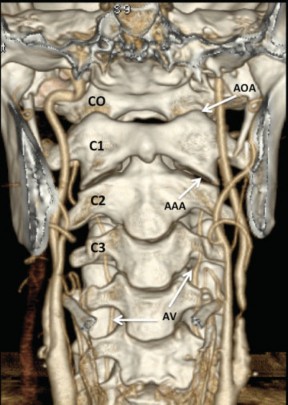

La UCC o charnela cráneo-raquídea está formada por los cóndilos del hueso occipital (CO), la 1ª vértebra cervical o atlas (C1) y la 2ª vértebra cervical o axis (C2). Por eso recibe el nombre de complejo occipito-atloido-axoideo (COAO). Esos 3 huesos están unidos por 5 complejos articulares: ambas articulaciones occipito-atloideas (AOA), la articulación atloido-odontoidea (AAO) y las articulaciones atloido- axoideas (AAA) (►Fig. 1). Por el lado de la base del cráneo es el hueso occipital el que contribuye a la UCC sobre todo por el foramen magno y los CO que se sitúan a sus lados.

Tomografía computada multi-detector (TCMD), VR, vista anterior. En el estudio se observa una visión global del sector superior del raquis cervical, vista anterior, con especial interés en la UCC. Se destacan las estructuras que la componen y sus articulaciones, así como las relaciones vasculares. Abreviaciones: AAA, articulación atloido-axoidea; AOA, articulación occipito-atolidea; AV, arteria vertebral; CO, cóndilo occipital; C1, 1ª vértebra cervical; C2, 2ª vértebra cervical; C3, 3ª vértebra cervical.